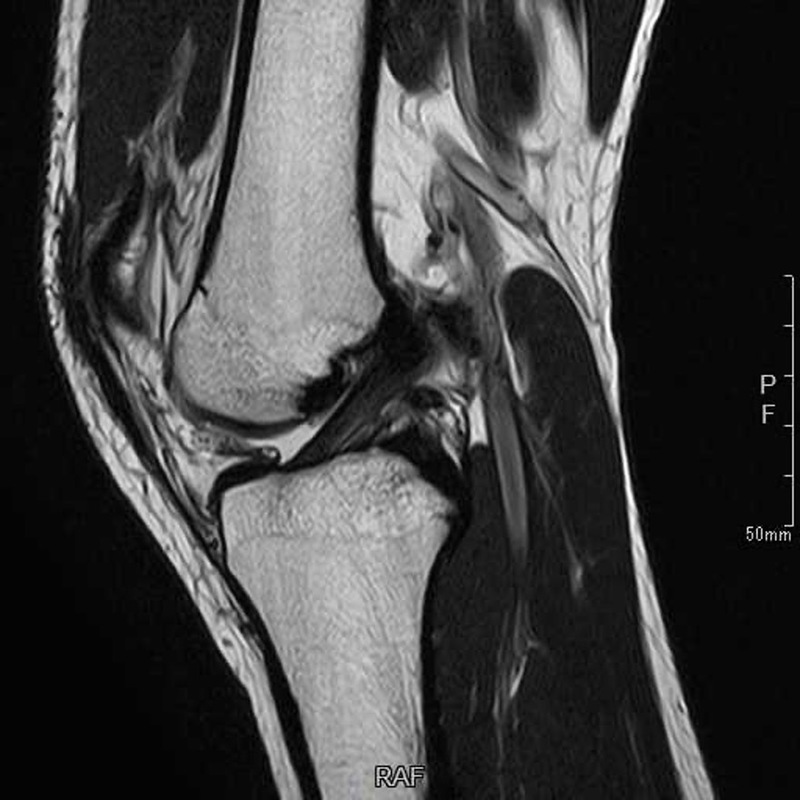

前十字靭帯を損傷するスポーツの場面は大きく分けて2種類あります。ラグビーなどのように相手に膝に直接タックルされることや、バスケットボールなどでジャンプの着地時に相手に直接的に膝に乗られてしまうなど膝に直接外力がかかり前十字靭帯が損傷する接触型の損傷といいます。もう一つの種類はサッカーなどのステップ動作中や体操競技の着地時に膝をねじってしまうことで膝に直接外力がかからない状況で前十字靭帯が損傷する非接触型の損傷です。前十字靭帯が損傷するとレントゲン画像だけではわかりませんが、MRIは大きく変わります。正常な前十字靭帯は黒く太いものがうつっていますが、損傷すると靭帯の連続性がなくなったり、靭帯がはっきりうつらなくなります。